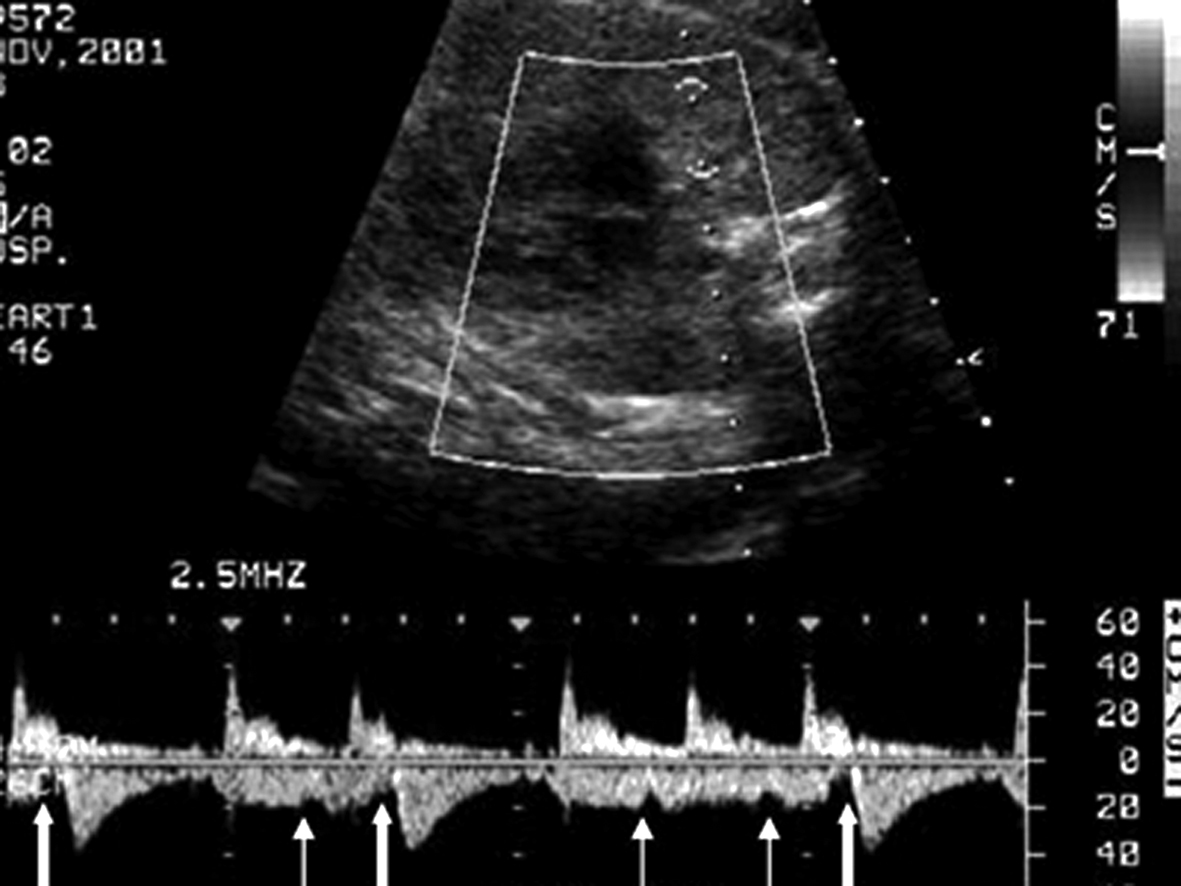

1.将取样门置于左室流入道和流出道交汇处,同时记录心室舒张期的二尖瓣(左室流入道)血流时间流速曲线和收缩期的左室流出道血流时间流速曲线,二尖瓣血流的A峰可反映心房的收缩期(图1)。此多普勒时间流速曲线关系反映了心房心室收缩的依从关系,当出现期前收缩或房室传导阻滞时,该依从关系发生改变。

图1 左室流入道、流出道血流时间流速曲线:E峰、A峰代表心脏舒张期,S峰代表心脏收缩期

图2 肺小动、静脉血流时间流速曲线:箭头所指处代表心房收缩